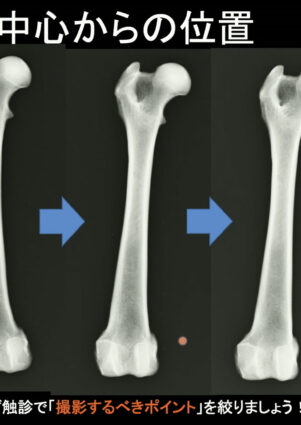

整形外科X線検査〜ポジショニングのポイント1〜「撮影の基本」

日常診療していると診察で見かけることのある動物の跛行。そんな時、跛行しているしとりあえずレントゲン撮っておこう。何かわかるかもしれないしというフランクな感じで撮っていることがありませんか?こちらの映像では、そんなX線の最も有用な使い方について、、、